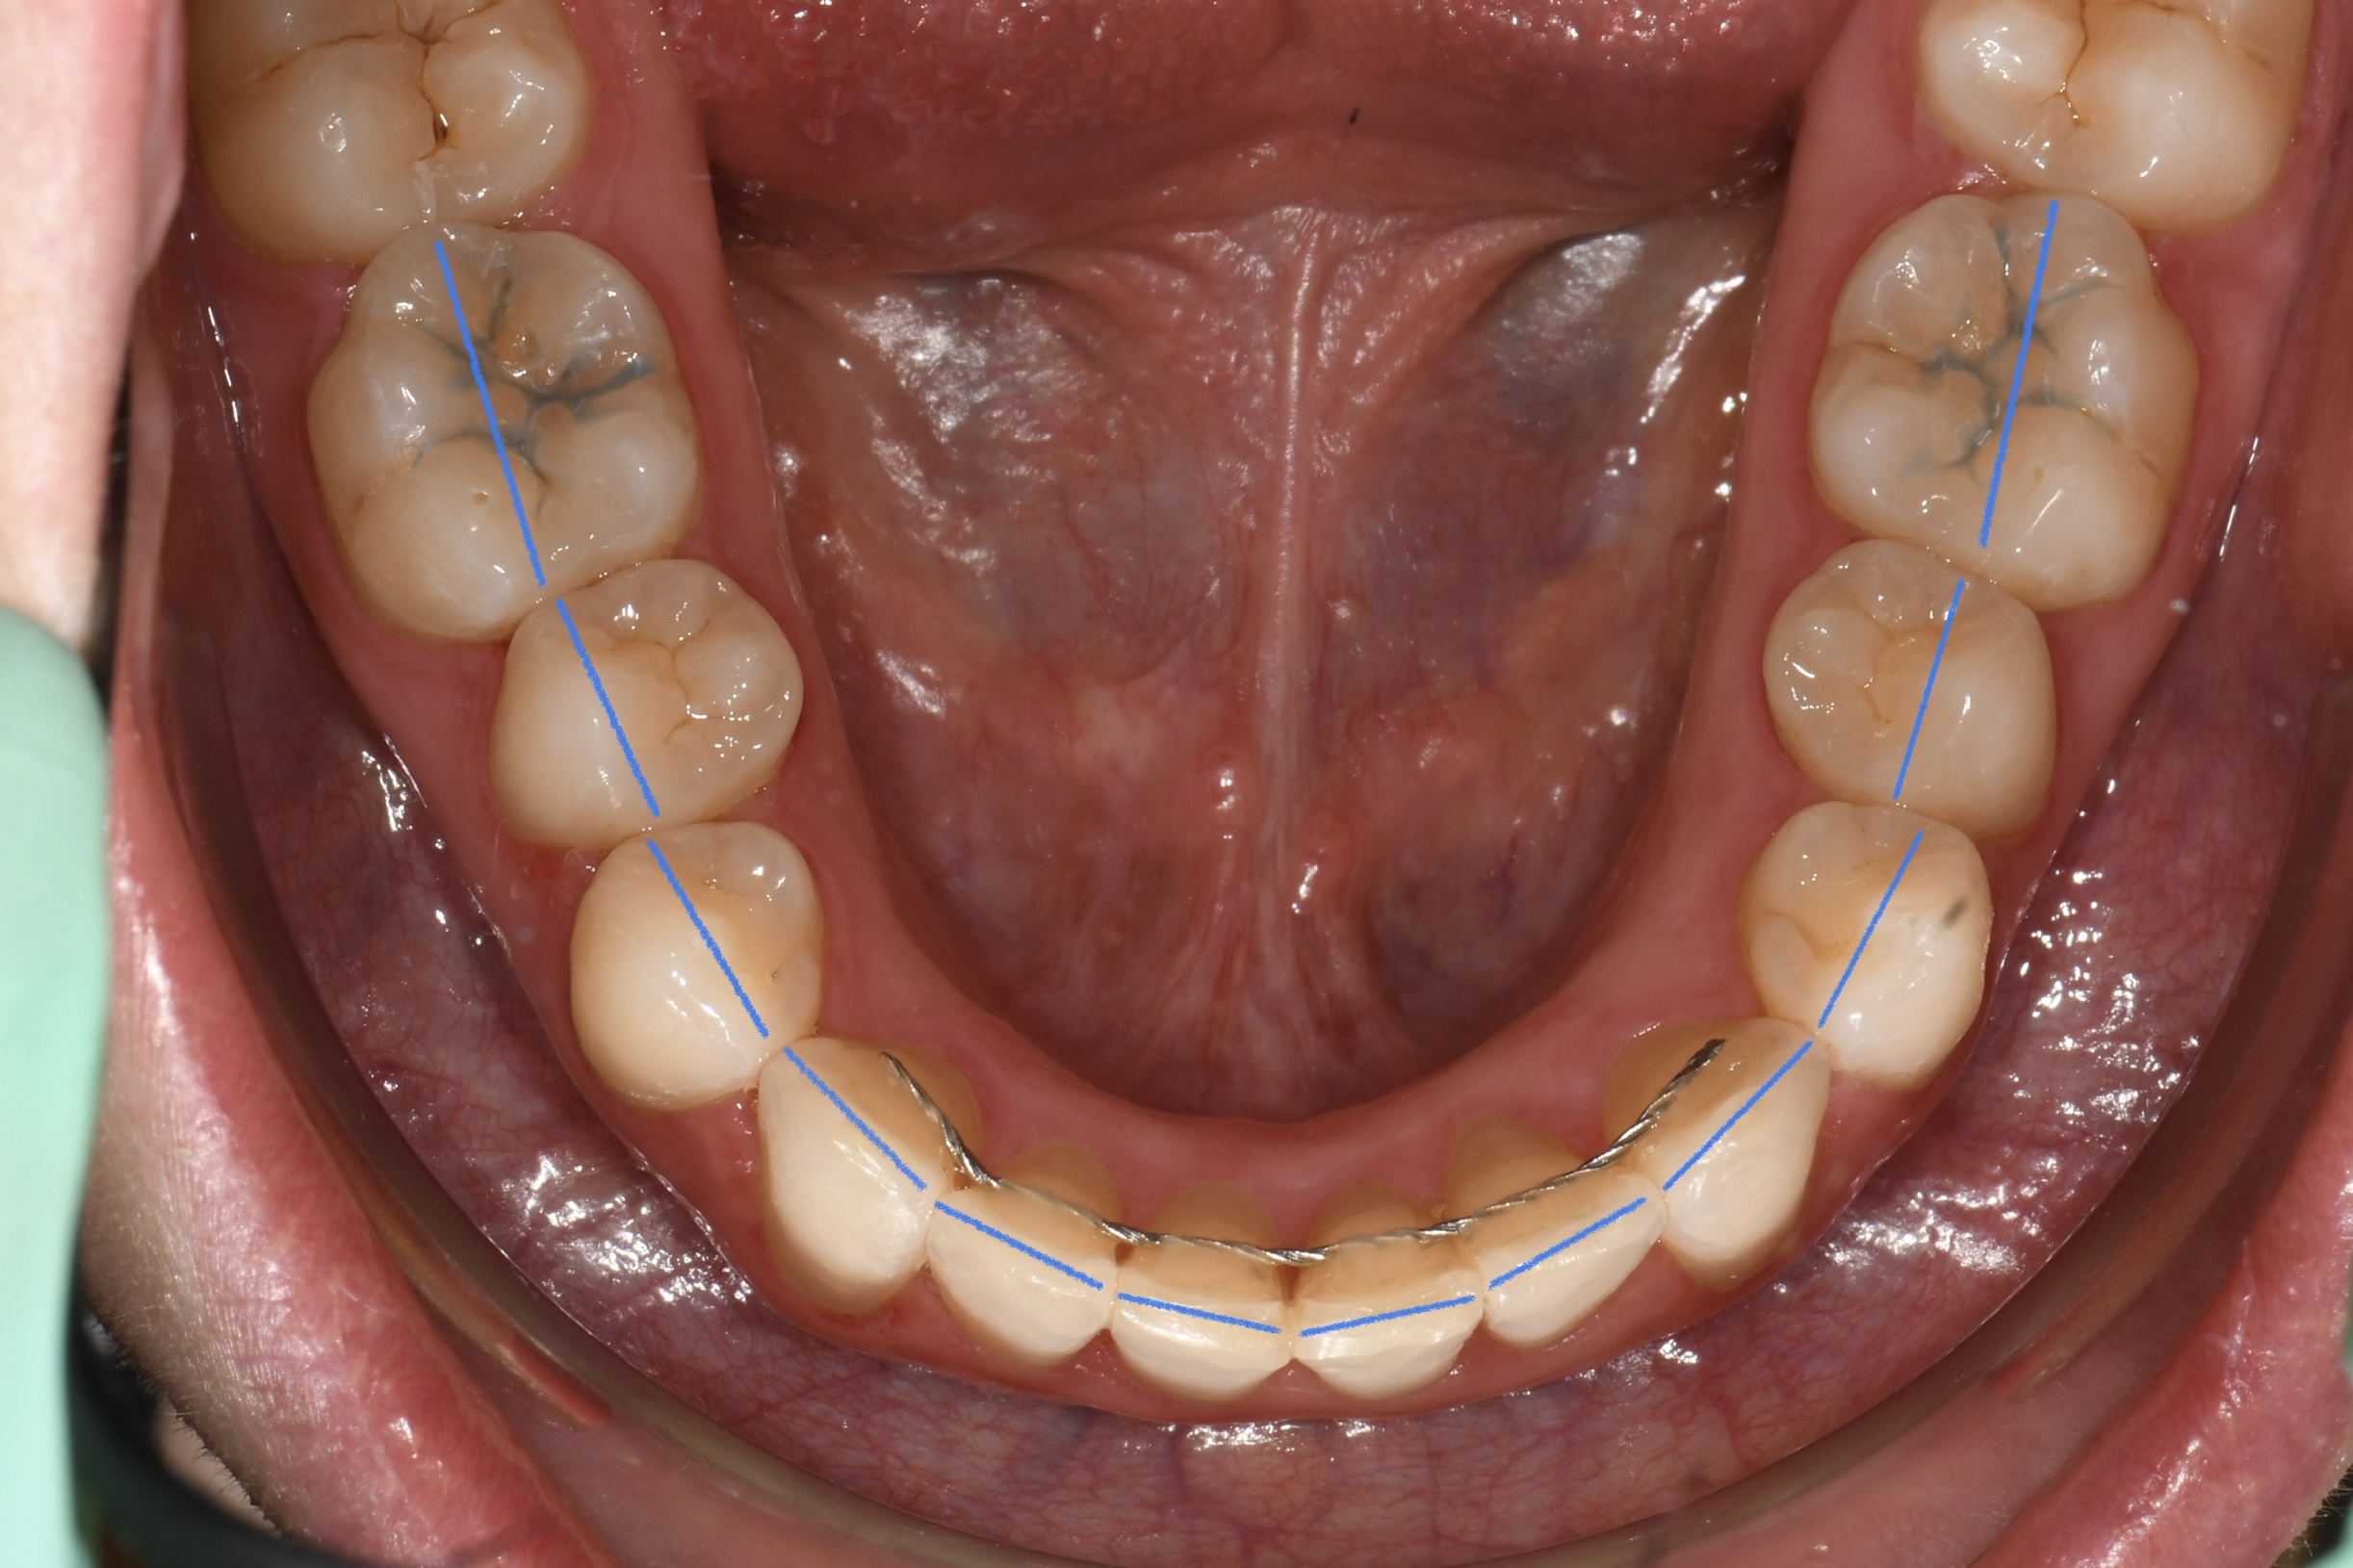

Az elmúlt évekből rengeteg szakmai referenciát tudnánk bemutatni, amelyek különböző fogszabályozási problémákat oldottak meg. Válogatva a több száz esetből, ezen az oldalon olyan képeket, információkat igyekeztünk bemutatni, amelyeknek a segítségével a jövőbeni pácienseinknek azt tudjuk üzenni: A Te fogsorod is lehet gyönyörű!

(Képeket a Pácienseink külön írásos beleegyezésével mutatjuk be!)